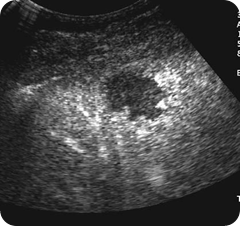

A haemangioma is demonstrated in the anterior part of

the right lobe of the liver

Larger ones can demonstrate a spectrum of reflectivity depending on their composition and may demonstrate pools of blood and central areas of degeneration. They frequently exhibit slightly increased through-transmission, with posterior enhancement, particularly if large. This is probably

due to the increased blood content compared with the surrounding liver parenchyma (Fig. 4.9).